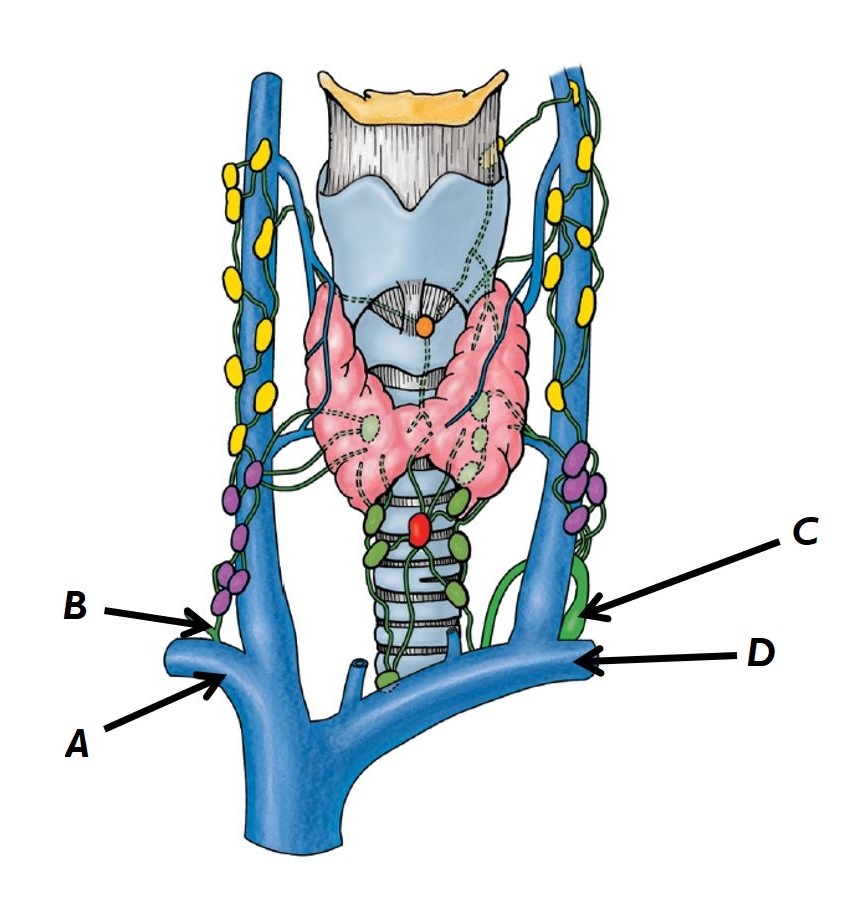

Name structures A to D

A - Common carotid artery

B - Internal jugular vein

C - Vagus nerve

D - Deep cervical lymph nodes